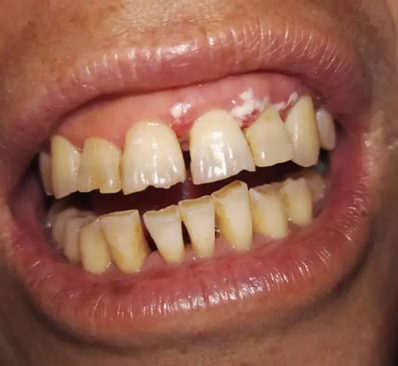

處置:首先進(jìn)行常規(guī)的牙周刮治,治療效果已經(jīng)很明顯,見圖片。